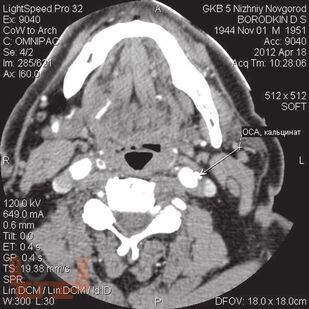

В пособии представлен не только хирургический раздел, но и анатомия кровообращения головного мозга и неврологическая симптоматика цереброваскулярных нарушений при атеросклеротических каротидных поражениях, поскольку каротидная хирургия неразрывно связана с этими аспектами. Приводится алгоритм обследования больных, охватывающий все современные методы нейровизуализации с указанием уровней доказательности, чувствительности и специфичности каждого из них. Особый акцент сделан на ценности ультразвуковых методов, которые наиболее доступны в клинической практике и достаточно информативны. При изложении лучевой семиотики для иллюстрации основных ангиоморфологических изменений даны эходопплерограммы, ангиограммы. Подробно описаны показания к хирургическому лечению, различные методы реконструкции сонных артерий.